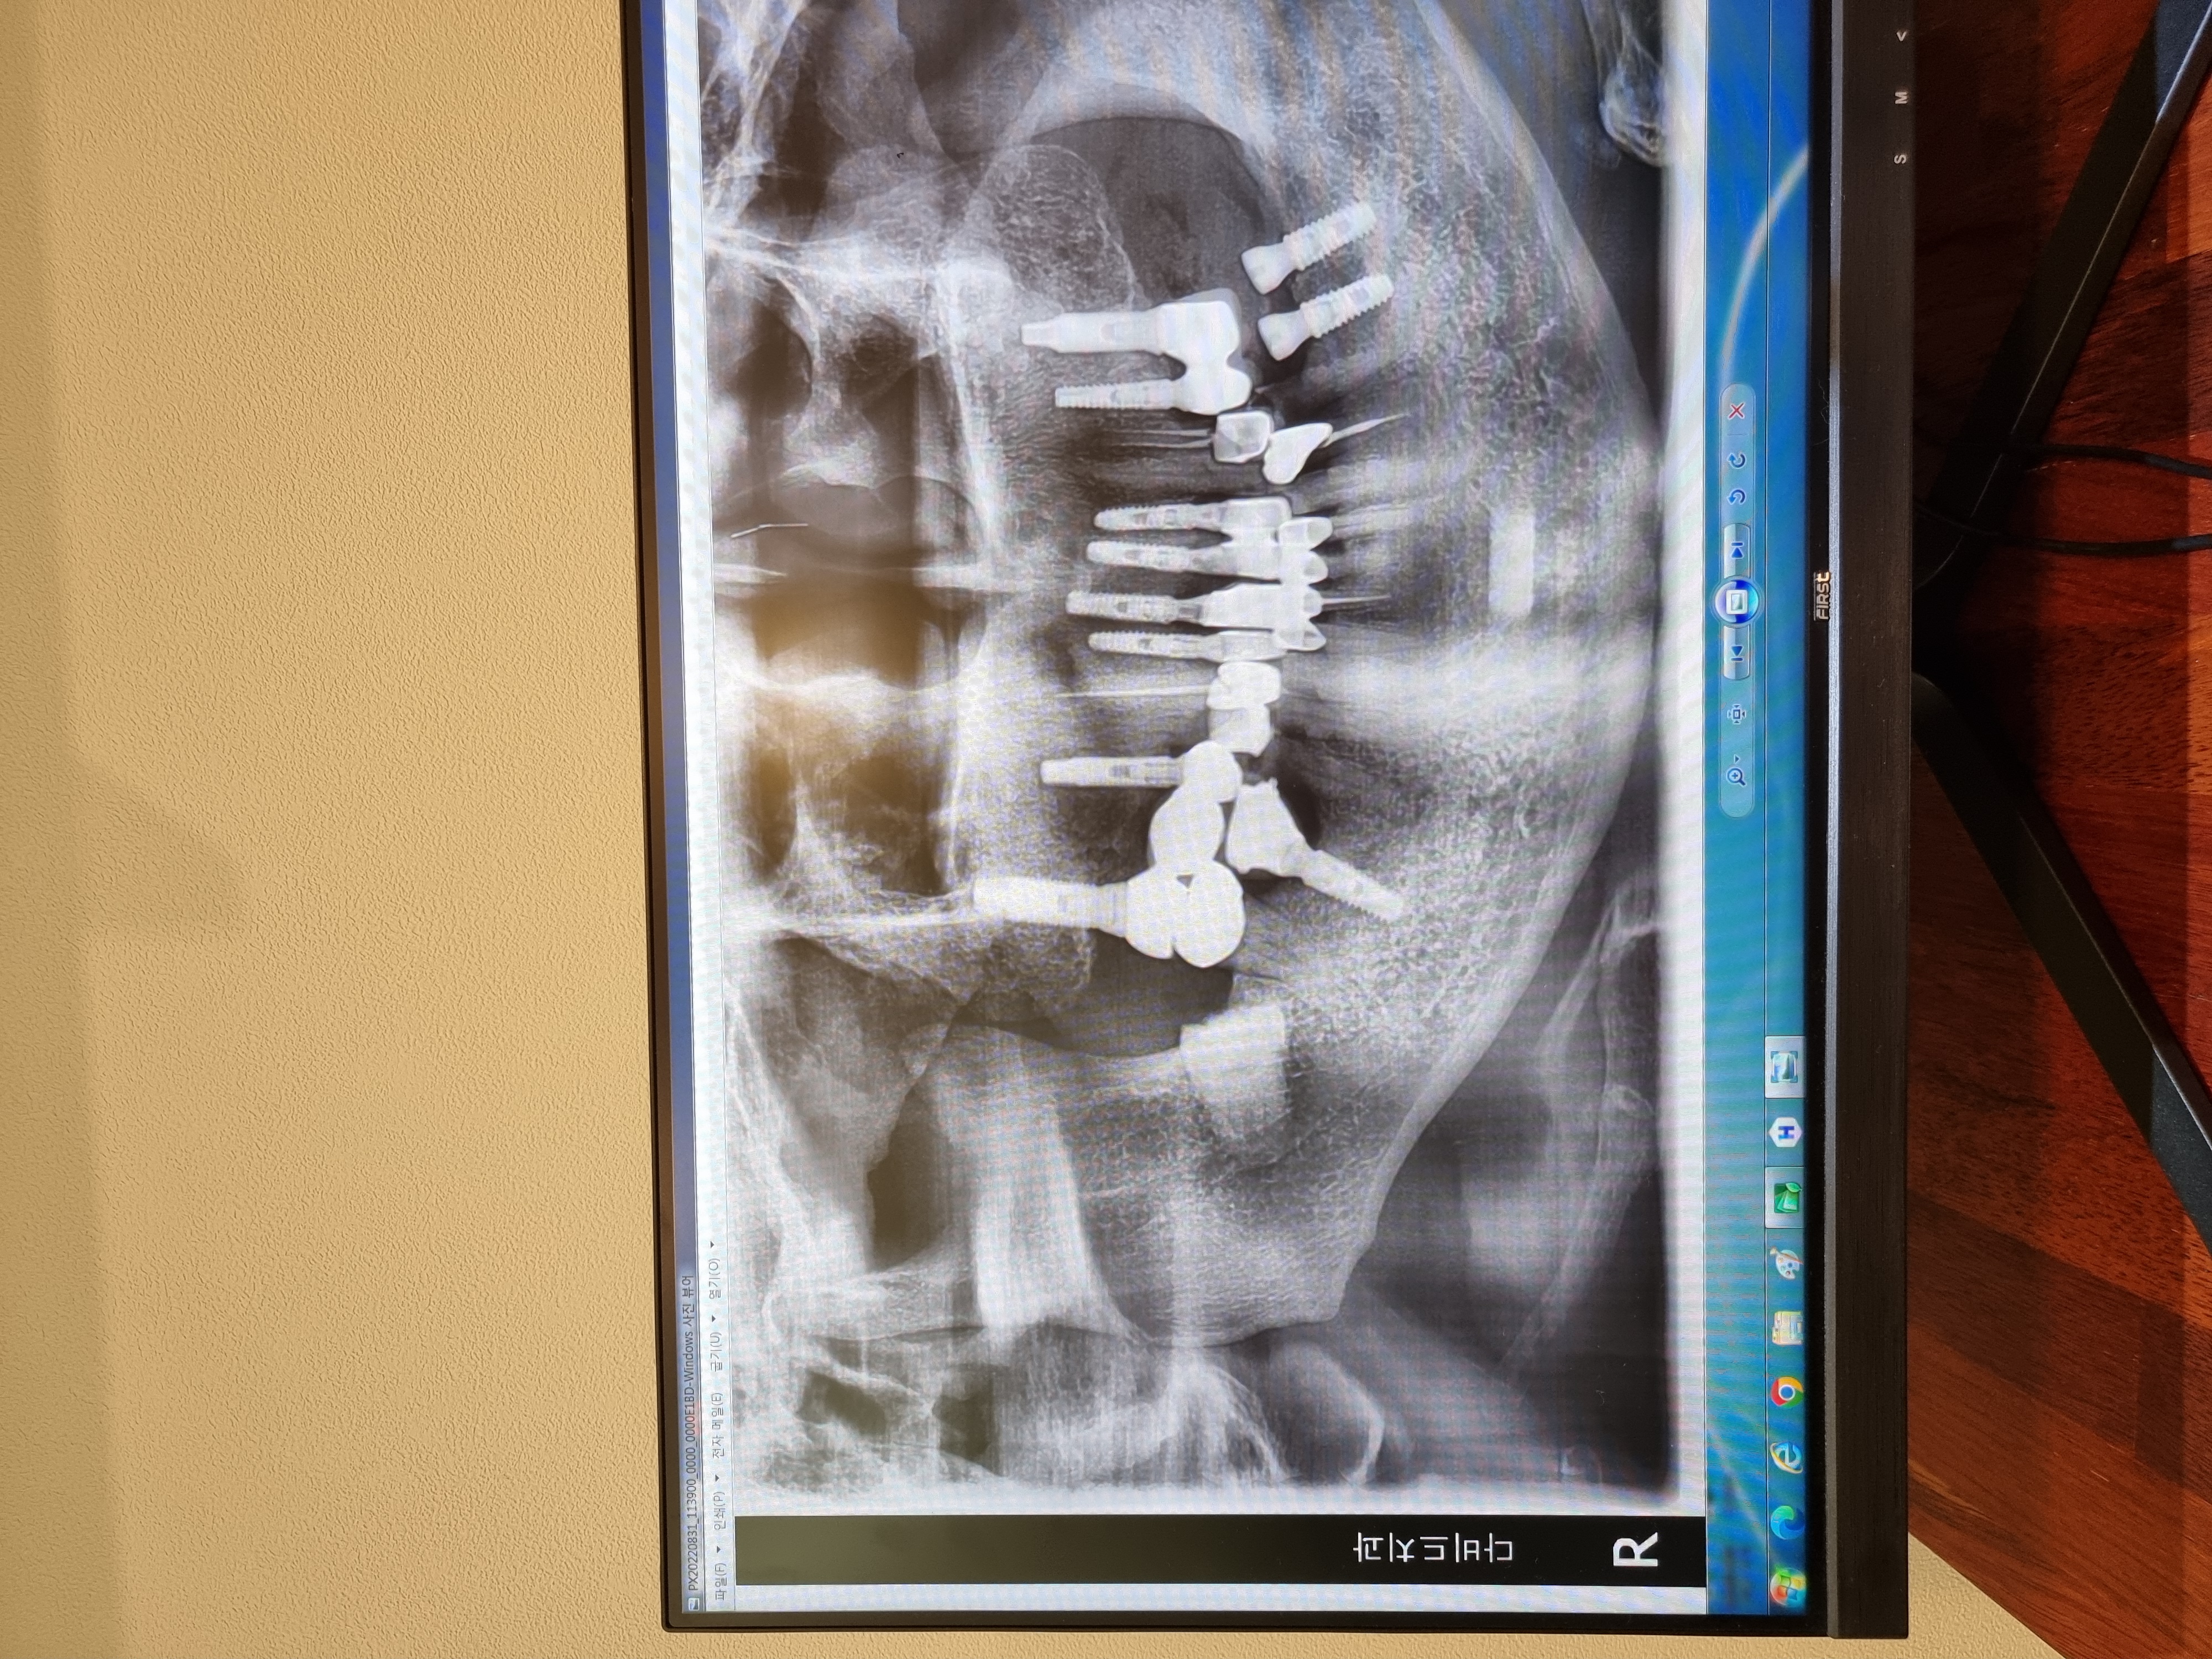

경기도 화성에 거주중인 48세 남성입니다. 캐시닥을 통해 다비드치과를 알게 되었습니다. 간단한 전화 상담 후 내원하여 검진 후 임플란트 시술을 결정하였고 당일 동네 병원보다 거의 40%저렴한 가격에 뼈이식과 7개 임플란트 식립까지 마쳤습니다.